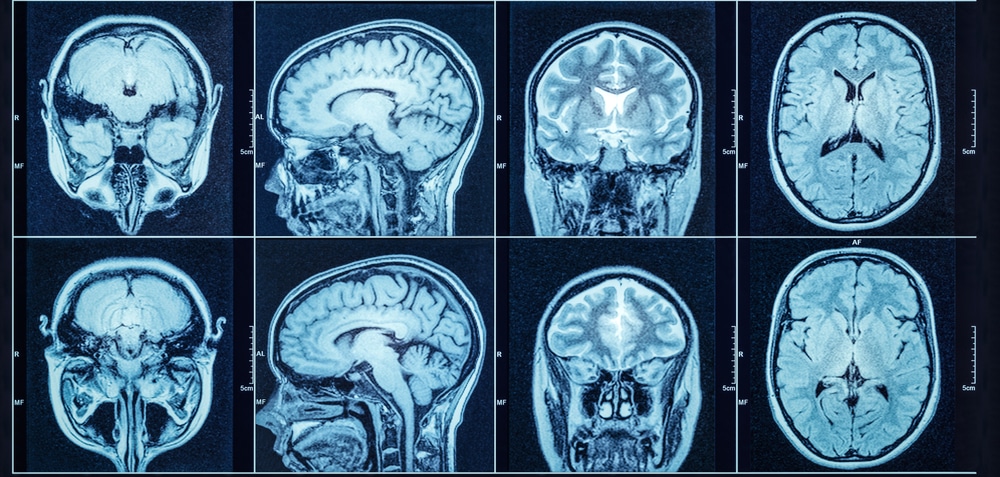

Neuroimaging: Small Findings Need Big Samples

When magnetic resonance imaging (MRI) provided the first detailed images of brain structure three decades ago, there was every reason to believe that this technique would reveal the brain changes associated with mental illness and transform clinicians’ ability to make a diagnosis. Yet remarkably, MRI is still not a standard tool for psychiatry, except to rule out a brain injury.

Scott Marek from Washington University and colleagues recently took a close look at the MRI literature to understand why this powerful imaging tool has still not yielded findings that are clinically actionable. They note that MRIs have helped identify the functions that certain structures of the brain perform and can be useful for following the progress of individual patients over time. But brain structure is so variable between people that studies comparing individuals have generally been too small to find reproducible differences.

Marek’s group wanted to determine the minimum number of subjects needed to provide meaningful, reproducible imaging results. They plumbed three large datasets of brain MRIs with a total sample size of around 50,000 people and drilled down into much smaller subsamples. Even though most published MRI studies report findings from less than 100 subjects, Marek and his team found that reports based on hundreds of subjects yielded inflated group differences and could not be replicated.

Based on their research, they contend that sample sizes need to be in the thousands to provide useful, reproducible data. They balance this sobering finding a bit by noting that smaller studies that combine a specific type of imaging known as functional MRI (fMRI), which looks at brain oxygen consumption as a measure of function, and studies that add other data such as cognitive testing, appear to provide more robust comparisons between groups.

These findings are similar to those in genomics, where scientists have needed large samples to find small effects. These studies remind us that individual variation in both genes and brains, like individual variation in personality, is part of the human condition. Finding consistent differences requires narrowing the focus to very small changes that may only be detectable with huge samples.

If MRI requires thousands of subjects to find reproducible differences, it seems unlikely that this can be a reliable clinical tool to guide decisions for diagnosing or treating an individual patient. The technique is still important for ruling out structural lesions and fMRI continues to hold promise for research. But the promise of 30 years ago has not been realized. Thankfully, electroencephalography (EEG), cognitive testing, new kinds of behavioral assessment, and clinical interviews continue to offer the possibility of greater diagnostic precision.